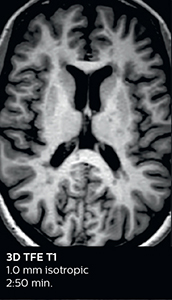

The choice for two Elition scanners was not made lightly. Dr. Savatovsky and his team compared devices from different vendors before making the decision. “Part of this process was our assessment of the image quality of different devices. We put together a list of sequences with detailed requirements, including limited acquisition times, to allow a fair comparison. We even put the same volunteer in each scanner. Our assessment was that the image quality was better with the Elition scanner. Compressed SENSE or Multiband SENSE was used for almost every sequence, and I think this helped a lot to maintain a great image quality in the shorter acquisition time.”

According to Dr. Savatovsky, Ingenia Elition has an impact in virtually all examinations. “We can either make the scanning faster compared to our older Ingenia 3.0T, or we save enough time so that we can add sequences we wouldn’t perform otherwise, or increase resolution. So, I think it has benefits for most of our patients.” “Some routine exams that we use every day have been shortened since we started using Elition. For example, we now use mostly a comprehensive stroke protocol (high b-value diffusion, fast 3D FLAIR, TOF, supra-aortic vessels angiography, SWIp, T1 post gad) that lasts 10 to 11 minutes, but our fast stroke protocol takes only 7 minutes. Our routine IAC needs about 10 minutes scan time and our comprehensive brain MS examination requires no longer than 13 minutes of scan time. Our ability to reduce acquisition times of most sequences helps to shorten total examination times, which in turn helps us to increase the number of patients we scan per day. “The main breakthrough for us was that Compressed SENSE and Multiband SENSE have allowed us to accelerate our examinations. Alternatively, we can invest the time gained in obtaining higher spatial resolution to see more details, or we can add additional sequences,” says Dr. Savatovsky. “That’s a big improvement from what we did before.”

A two year follow-up scan of a CPA meningioma using both Ingenia 3.0T without CS and Ingenia Elition 3.0T with Compressed SENSE allows for a nice comparison to demonstrate the protocol improvements achieved on the Elition: 3D FLAIR has a shortened scan time, improved SNR and still the same spatial resolution. BrainView (3D T1 TSE) has improved spatial resolution and SNR with shortened scan time. For 3D T2 Drive the spatial resolution has been improved. 3D THRIVE used to have an interpolated 0.8 mm slice thickness, but true thickness at 1.6 mm, so that axial slices displayed a decent quality, but reformats were suboptimal. Compressed SENSE is used on Elition to improve spatial resolution and reduce the non-interpolated slice thickness to allow smoothly reformatted images. Total scan time (adding SmartBrain and an additional b2000 diffusion) was 13:19 on Ingenia, and is now reduced to 10:42 on Ingenia Elition.

Ingenia 3.0T (without Compressed SENSE)

3D FLAIR 1.0 x 1.0 x 1.0 mm* 4:24 min.

3D TSE T1w 1.0 x 1.0 x 1.2 mm* 2:40 min.

3D T2w Drive 0.8 x 0.8 x 1.0 mm* 3:05 min.

3D T1w THRIVE 0.8 x 0.8 x 1.6 mm* 1:30 min.

Ingenia Elition 3.0T with Compressed SENSE

3D FLAIR 1.0 x 1.0 x 1.0 mm* 2:50 min.

3D TSE T1w 1.0 x 1.0 x 1.0 mm* 2:10 min.

3D T2w Drive 0.7 x 0.7 x 0.7 mm* 2:52 min.

3D T1w THRIVE 0.7 x 0.7 x 0.8 mm* 1:30 min.

*true voxel size, without interpolation